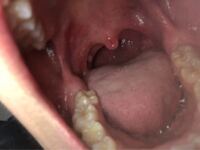

喉の写真あります すごく喉が痛いです 唾を飲み込む時が Yahoo 知恵袋

お見苦しい写真すみません 三日くらい前から 物を飲み込むと喉が痛 Yahoo 知恵袋

画像注意唾を飲み込む時に少し喉が痛いなと思って見てみたら白 Yahoo 知恵袋

閲覧注意最近飲み込む時に喉が痛みます いつも風邪を引く時は喉から Yahoo 知恵袋